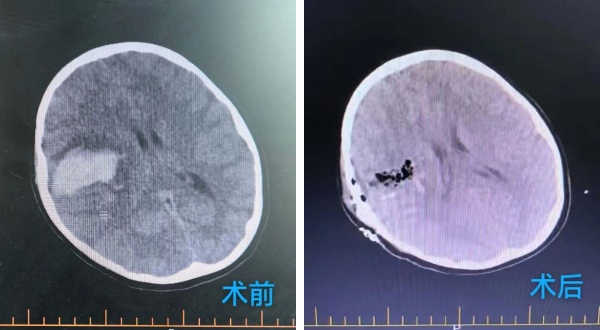

2025年9月8日,活泼好动的8岁小男孩小雨(化名)在无任何明显诱因下,突然出现剧烈头痛,随后左侧肢体完全无法活动,并且短时间内出现嗜睡情况且持续加重,期间呕吐多次。家人紧急将其送至当地医院,当地头部CT检查结果如同晴天霹雳——“右侧颞叶脑出血”。为寻求进一步救治,家人当机立断,带着小雨连夜奔赴北京,被我院急诊以“右侧脑出血、肢体活动障碍”紧急收治于北京航天总医院神经外科。

庞克军主任医师紧急启用神经外科绿色通道,导管室协助,由神经外科医师紧急行脑血管造影术检查,检查快速且准确,可以看见小雨颅内是有动脉畸形,并且是2处!

我院神经外科团队学科讨论后一致认为小雨必须立即进行开颅手术,清除血肿、处理畸形血管团,以解除对脑组织的压迫,为患儿争取最大的康复希望。

在麻醉科协助下,手术显微镜下动静脉畸形(AVM)不是单纯的肿瘤,而是一团异常缠绕的血管球,其内血流动力学极其紊乱,血管壁脆弱,极易在分离过程中破裂出血。然而小雨动脉畸形病灶位于“功能区”周围,意味着这团畸形的血管就是“镶嵌”在大脑控制对侧肢体运动、感觉甚至语言的核心区域,任何轻微的牵拉、电凝或血供干扰,都可能导致永久性的功能损伤,更危险的是儿童的脑组织尚在发育中,比成人更加娇嫩,对手术牵拉、缺血缺氧的耐受能力更差。庞克军主任医师以精湛的技术和极大的耐心,小心翼翼地清除了压迫脑组织的血肿,并以微米级的精度进行操作,沿着AVM与正常脑组织之间的“胶质带”进行分离,力求完好无损地剥离畸形团。整台手术操作精准、流畅,成功拆除了埋藏在小雨脑内的“炸弹”。

术后,小雨被送回我院神经外科病房进行密切监护。在医护团队不分昼夜的精心治疗和护理下,他平稳度过了术后危险期。令人欣喜的是,他的意识逐渐转轻,原本无法活动的左侧肢体也开始出现了自主活动。